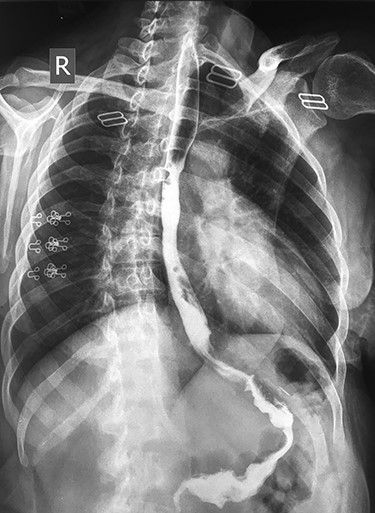

The patient underwent repeated endoscopic dilatation with successful dilatation at the end of the management (Fig. 2).

An endoscopic view showing (A) esophageal stricture before endoscopic dilatation, and (B) the site of the stricture after successful endoscopic dilatation.